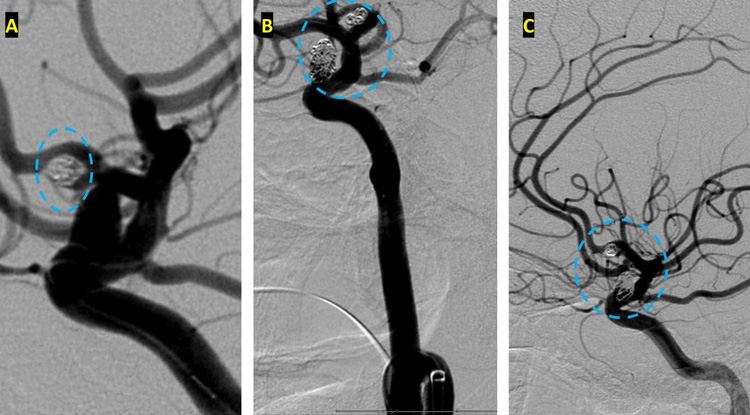

After careful measurements of the parent vessels, aneurysm sac, and aneurysm neck, we decided to proceed with Primary Coil Embolization of the Acom Aneurysm first, followed by the Right ICA Aneurysm next. Despite greater suspicion in the Acom region, a significant level of uncertainty remained, and we felt it was better to secure both aneurysms if capable of being performed safely. (Figure 4.)